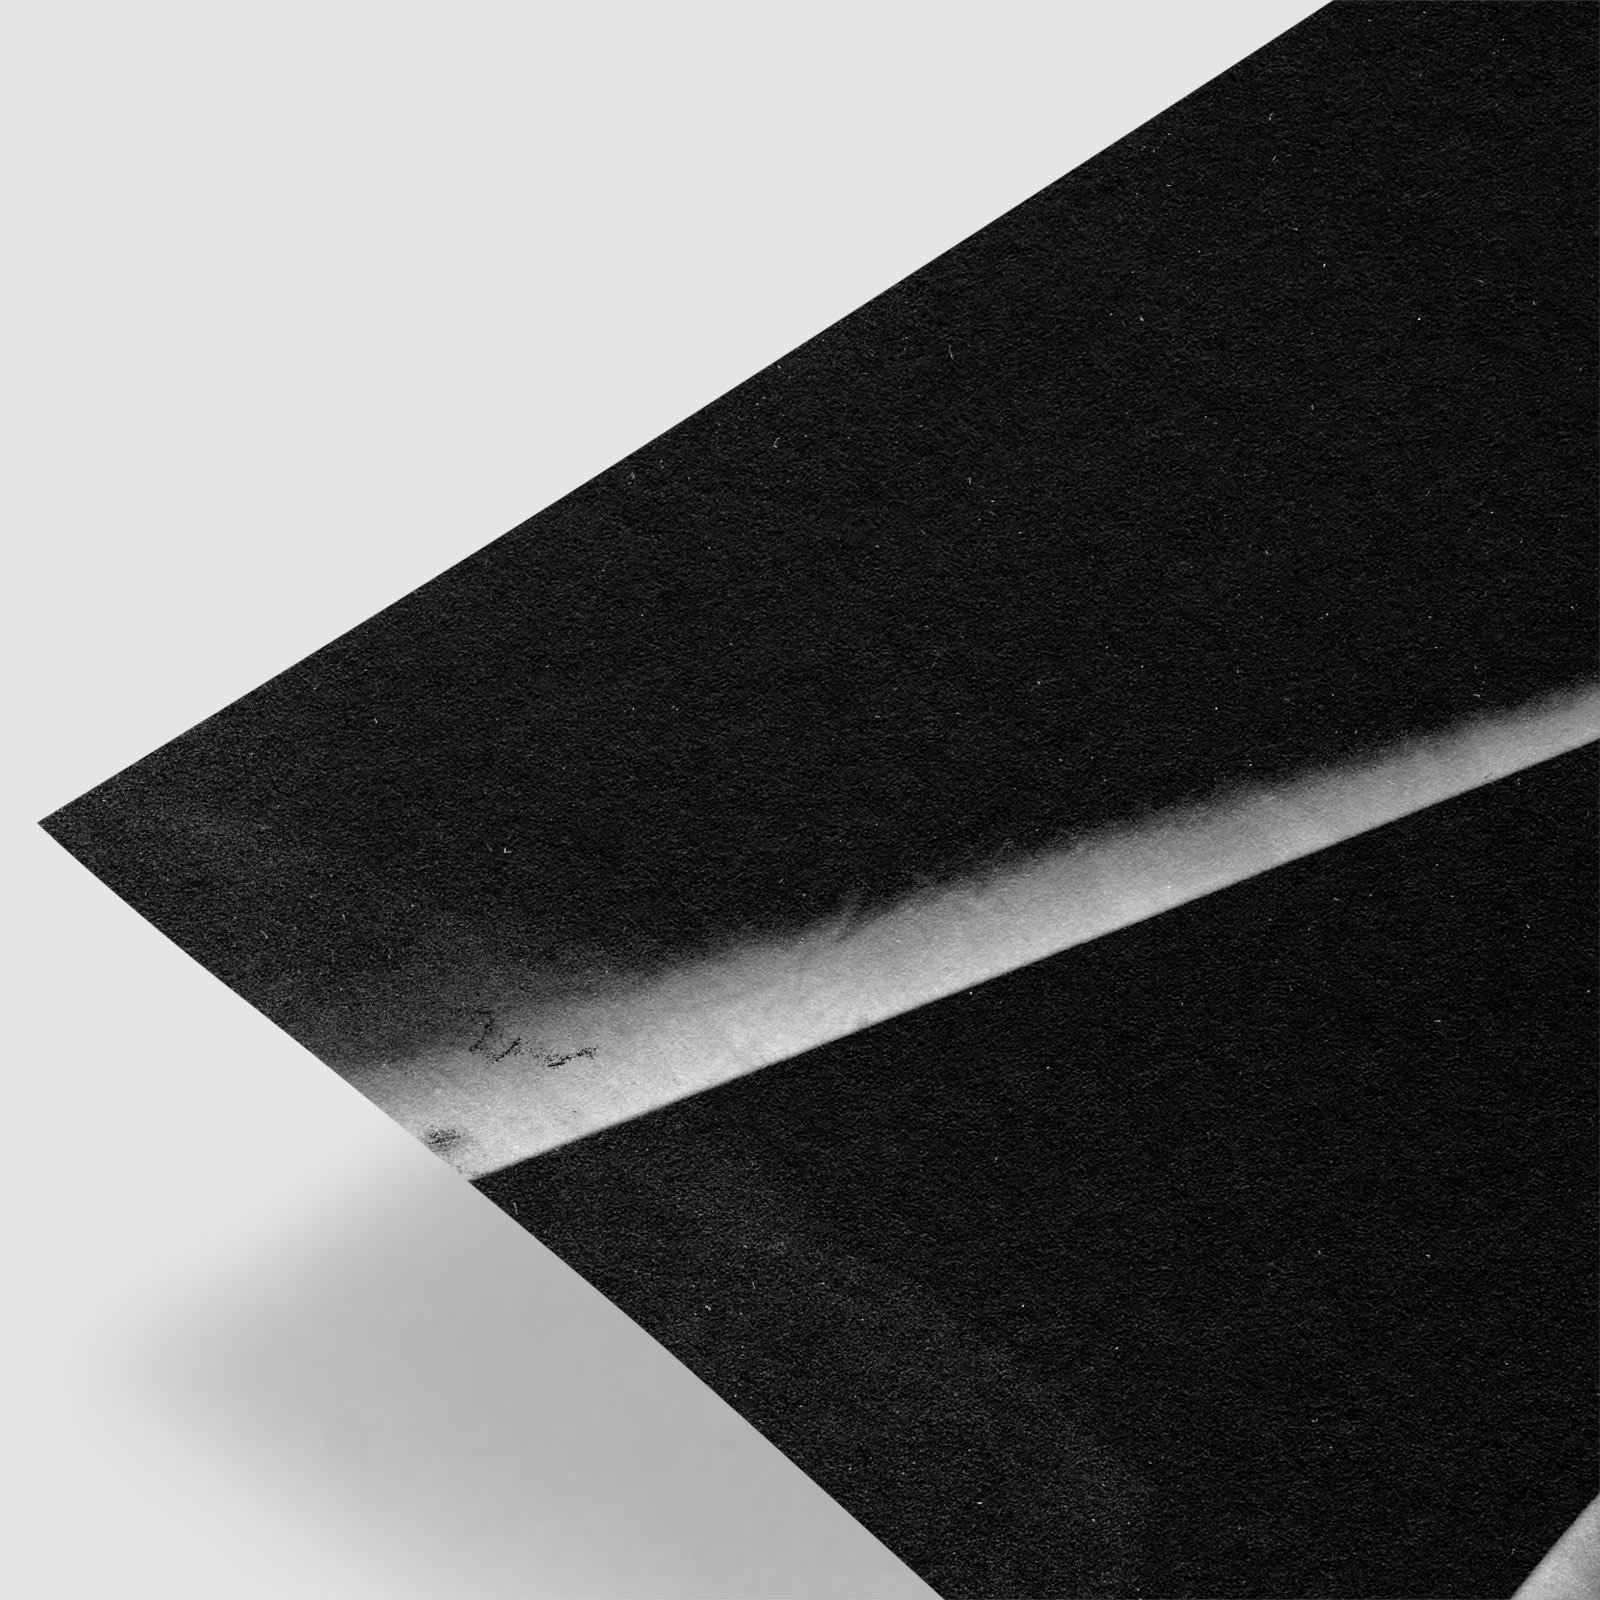

Properties of Human Heart by Augustus Waller 1888

Properties of Human Heart by Augustus Waller 1888

Properties of Human Heart by Augustus Waller 1888

Properties of Human Heart by Augustus Waller 1888

Plate from Augustus D. Waller’s Introductory Address on the Electromotive Properties of the Human Heart.

Augustus Desiré Waller (18 July 1856 – 11 March 1922) was a British physiologist renowned for his pioneering work in electrocardiography. In 1887, he recorded the first human electrocardiogram using a capillary electrometer. He went on to develop the first practical ECG machine with surface electrodes and presented his work across Europe and America—often using his dog, Jimmy, in live demonstrations.The Bull by Franz Marc (1912)